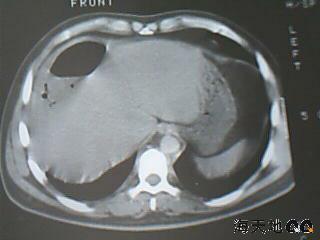

男 32y 外伤后一月余,现 t38.5,肝区隐痛。

右肝膈顶区液气平面.右膈肌增厚改变,病灶下部层面呈半月形延伸于肝表面.且于横结肠无明确密度切关系.

结合临床症状;考虑膈下脓肿.建议薄层矢状重建进一步证实.

鉴别;1,膈疝;2,间位结肠.

右隔肌与肝顶之间隙有长气液平,其下散在点状气体影,右侧腹膜局限增厚。考虑右膈下脓肿。

考虑右膈下脓肿。病灶不在肝内,位于肝外膈下;病灶下方的层面无结肠影与之相连。

右膈肌增厚,肝膈间见条状低密度影内可见积气影及宽大液平面,并未见与结肠相连。因此考虑膈下脓肿。